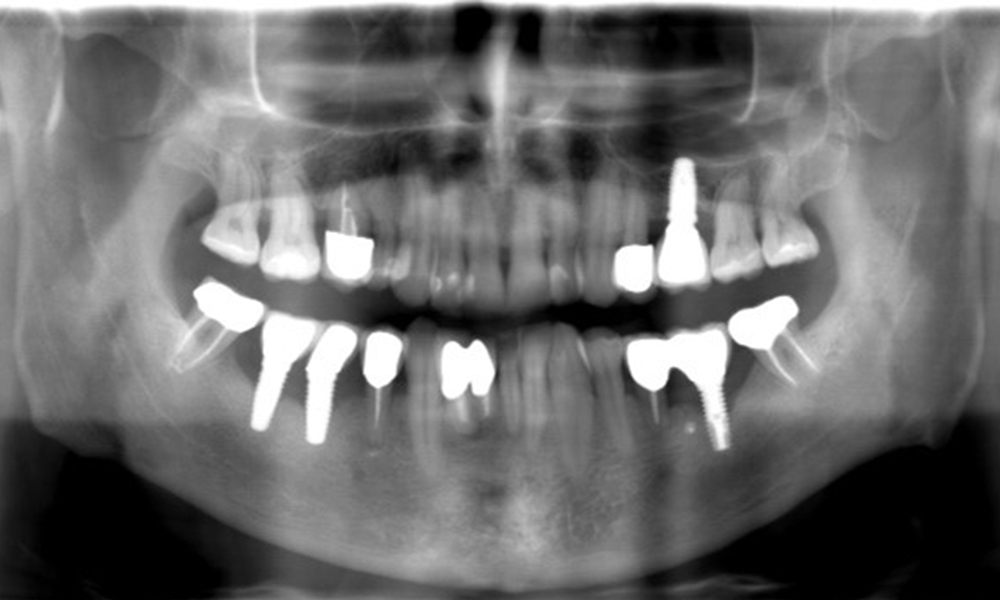

The X-ray images show the progression of bone loss.

The X-ray images show the progression of bone loss. OPG from 29.06.2020 (left) and OPG from 26.02.2024 (right).

OPG: 26/02/2024 Dental X-ray: 18/01/2024